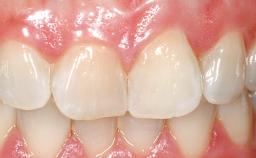

A 42-year-old female patient was referred to our clinic at the School of Dentistry of the University of São Paulo in November 2004, presenting a deficient restoration in the upper left central incisor. The clinical examination revealed no gingival retraction or any signs of gingival inflammation and, therefore, previous periodontal treatment was not considered. The patient presented a high lip line at full smile and a thin tissue biotype. This combination characterized a high-risk situation from an anatomic point of view, which required careful preoperative planning and cautious surgical execution.

Patient's Esthetic Expectations Low Medium High

Lip Line No exposure of papillae Exposure of papillae Full exposure of mucosa margin

Periodontal Phenotype Low-scalloped, thick Medium-scalloped, medium-thick High-scalloped, thin